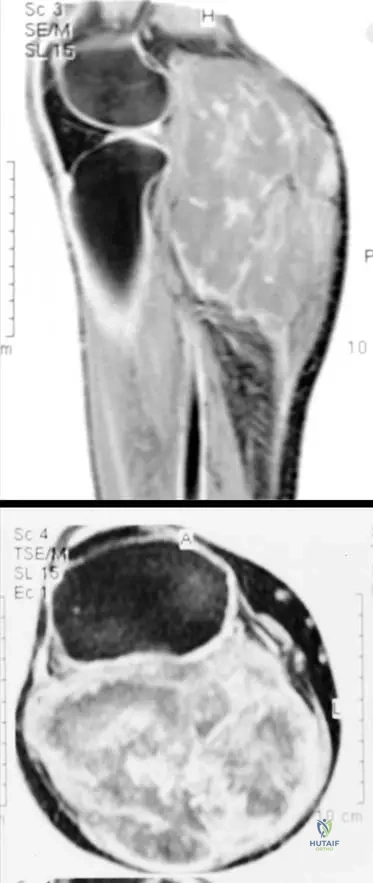

A 52-year-old male presents with a firm mass in his proximal forearm. An MRI is performed to evaluate the extent and characteristics of the lesion.

Correct Answer: A

Rationale: The clinical context for Fig. 9.15 states: "Axial T1(a) and T2-weighted image with gadolinium and fat saturation (b) showing a heterogeneous soft tissue sarcoma in the proximal forearm that is predominantly in the subcutaneous tissues abutting the adjacent myofascial plane." Main Distractor: B) Entirely within the deep muscular compartment. The image context explicitly states the lesion is "predominantly in the subcutaneous tissues," which contradicts a purely deep muscular location.